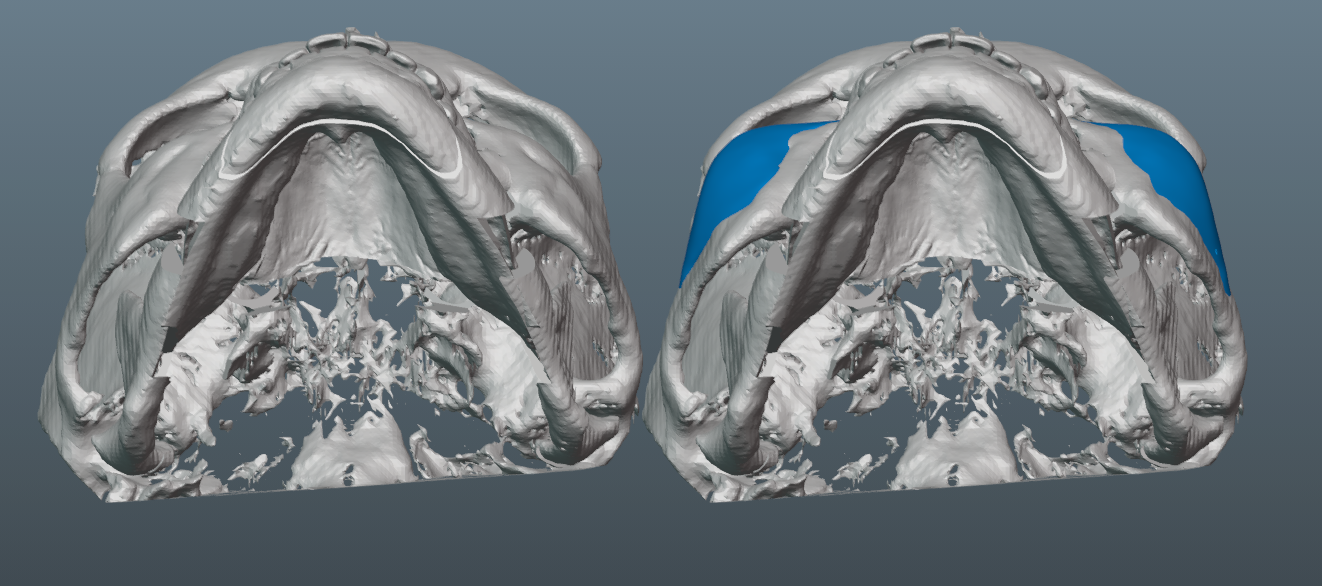

Needed a lot of projection on the malar part of the implant, since the patient has a fairly flat midface, which would have been exacerbated by the bimax.

-6mm malar projection.

-3mm saddle on the infras.

-Minimal projection on medial part of infra region. This helped keep the taper minimal and avoids too much of the infamous infra implant shelfing/step-off.

-Though we initially tried to do a smaller implant, it became clear that it was necessary to increase its size, so that we could ensure better transitions to the submalar region, zygo arch and lateral orbital rim.